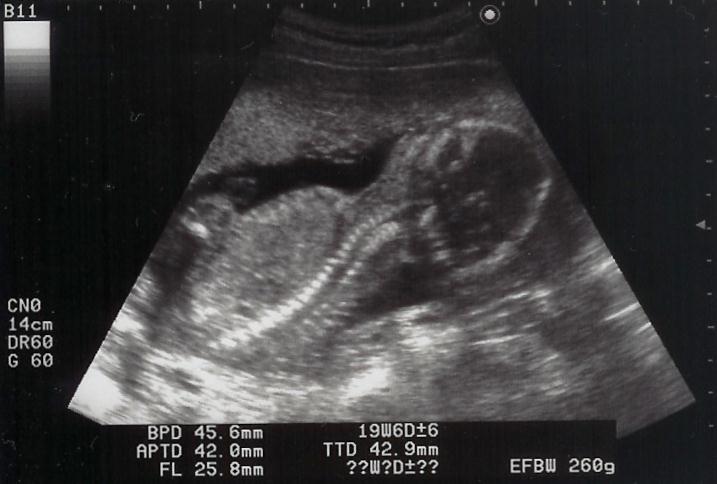

shigeruはとても元気に動いていて、心音を探すのが大変でした。エコーでは手をグーパーしながら、時々ママを見ていました。この写真は苦しそう?早く出てきたいの?でも、あと21週間はママのお腹にいてね。ママは体重が4週で1.6kg増。助産師さん・お医者様に注意されてしまいました。

仰向けでshigeruの形が判ります。

必見宇宙人!?こちらを凝視してます。